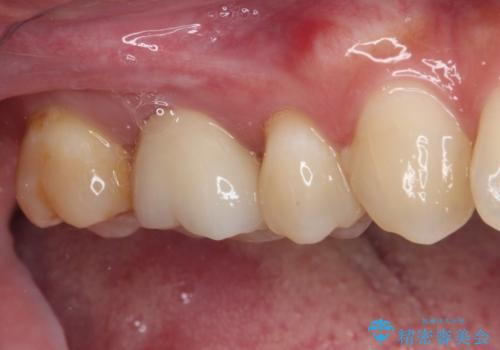

健全歯質が多いため、インレーおよびむし歯を除去した上で知覚過敏を緩和させる処置を行うことが望ましいと判断されましたが、知覚過敏の症状が一向に改善されないため、全体をセラミッククラウンで補綴することとしました。

セラミッククラウンを装着する前に仮歯を装着しましたが、その時点で強い痛みはほぼ改善され、セラミッククラウン装着後には痛みはもちろん、しみる症状も感じることがなくなりました。